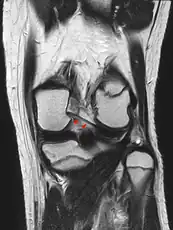

Posterior meniscofemoral ligament on MRI, coronal

The posterior meniscofemoral ligament (also known as the ligament of Wrisberg) is a small fibrous band of the knee joint. It attaches to the posterior area of the lateral meniscus and crosses superiorly and medially behind the posterior cruciate ligament to attach to the medial condyle of the femur.[1]

The posterior meniscofemoral ligament is found in 64.4% of the subjects in MRI scan of the knee.[1]